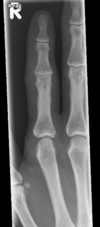

Fratura de Bennett

Fratura da base do primeiro metacarpo;

Intra-articular;

Dois fragmentos.